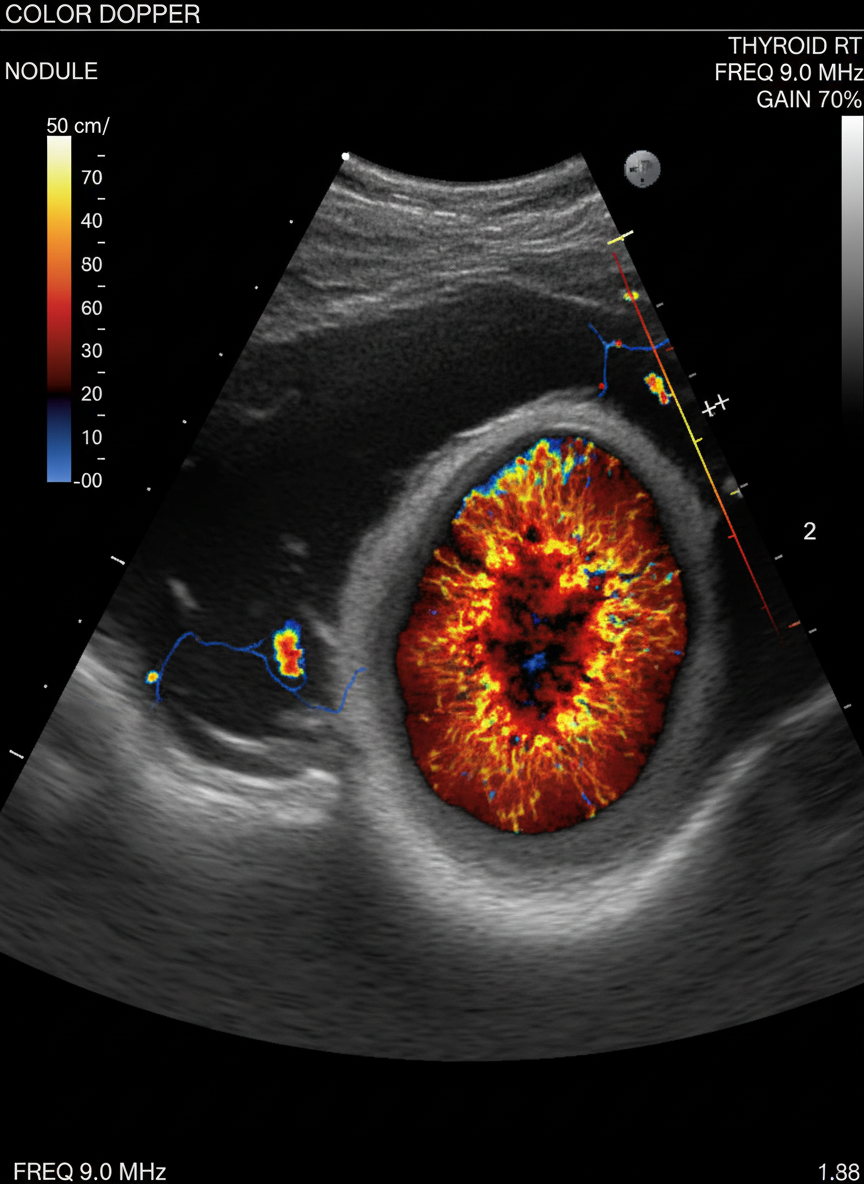

병원에 방문하면 보통 먼저 갑상선 초음파 검사를 하게 돼요.

이 검사는 통증 없이 빠르고 정확하게 갑상선의 상태와

결절의 유무, 크기, 모양 등을 확인할 수 있는 아주 유용한 방법이죠.